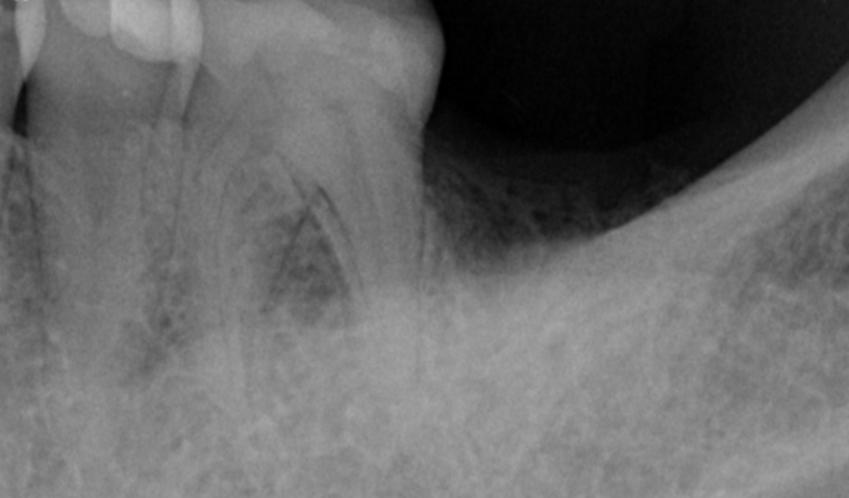

3. During the implant placement, a certain degree of bone and soft tissue deficiency was identified in the edentulous area. Consequently, bone graft (0.25g) and a collagen membrane were simultaneously placed.

Bone and soft tissue deficiency in the edentulous area